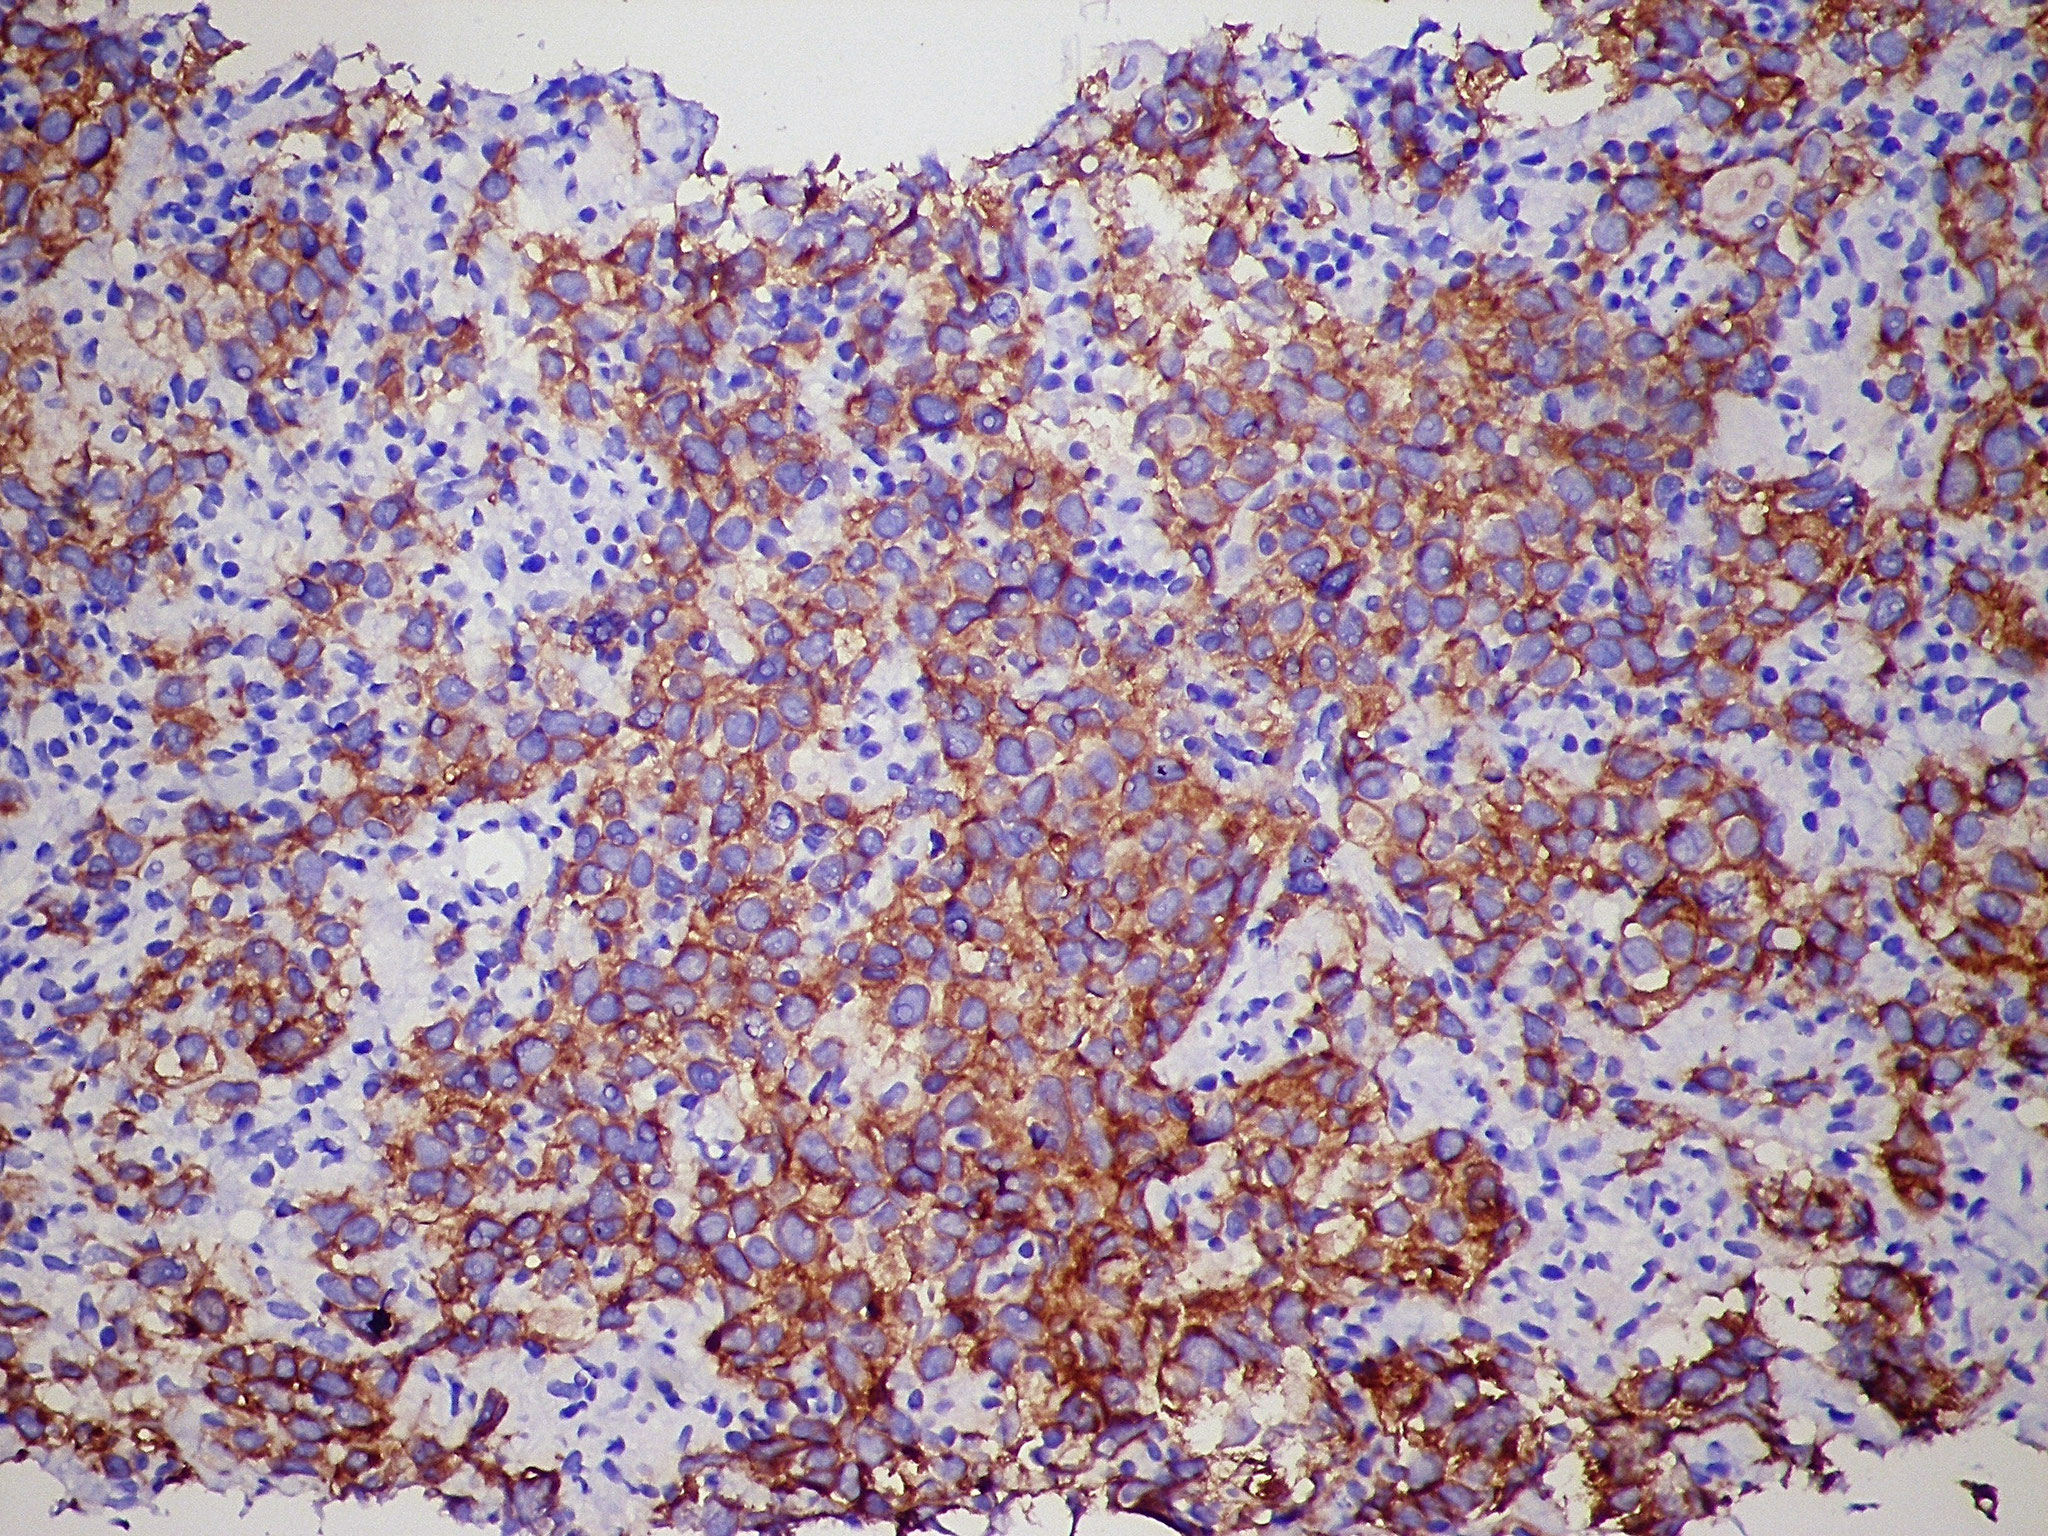

Patología Molecular

El diagnóstico sobre muestras de tejidos y líquidos corporales en plena era de la medicina del futuro, está basado en la integración de técnicas y conocimientos diferentes.

Hoy más que nunca es importante integrar una buena historia clínica con un correcto estudio de imagen y una buena morfología que además puede estar apoyada con proceso especiales complementarios relacionados con la Inmunología, Biología Molecular y Citogenética, generando así un estudio integral conocido como Patología Molecular.